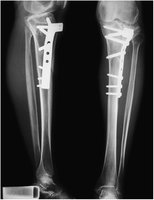

Internal Fixation

Severe fractures may require internal fixation with plates and screws to stabilize bone fragments during healing.